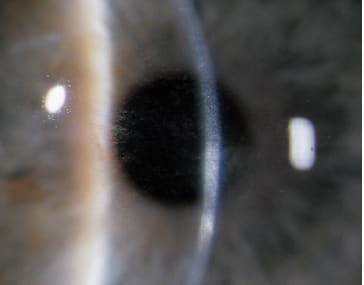

COURTESY OF UDAY DEVGAN, MD

Figure 1. Intraoperative view of femtosecond laser incisions in cataract surgery made with the Alcon LenSx. Note the presence of small gas bubbles under the anterior lens capsule and the larger, yellow-appearing gas pockets in and around the lens nucleus.

■ Anterior chamber gas bubbles. Gas rarely escapes into the anterior chamber, but it can cause issues when it does (Figure 1). Some researchers have speculated that air can occasionally track through Schlemm’s canal into the anterior chamber. I have previously reported that anterior chamber air bubbles resulting from a femtosecond laser do not affect endothelial cell density when compared to normal eyes in a large series.4 The bubbles can affect tracking in certain lasers, and you can either dilate and track while the pupil is enlarging, or wait for the bubbles to resorb.